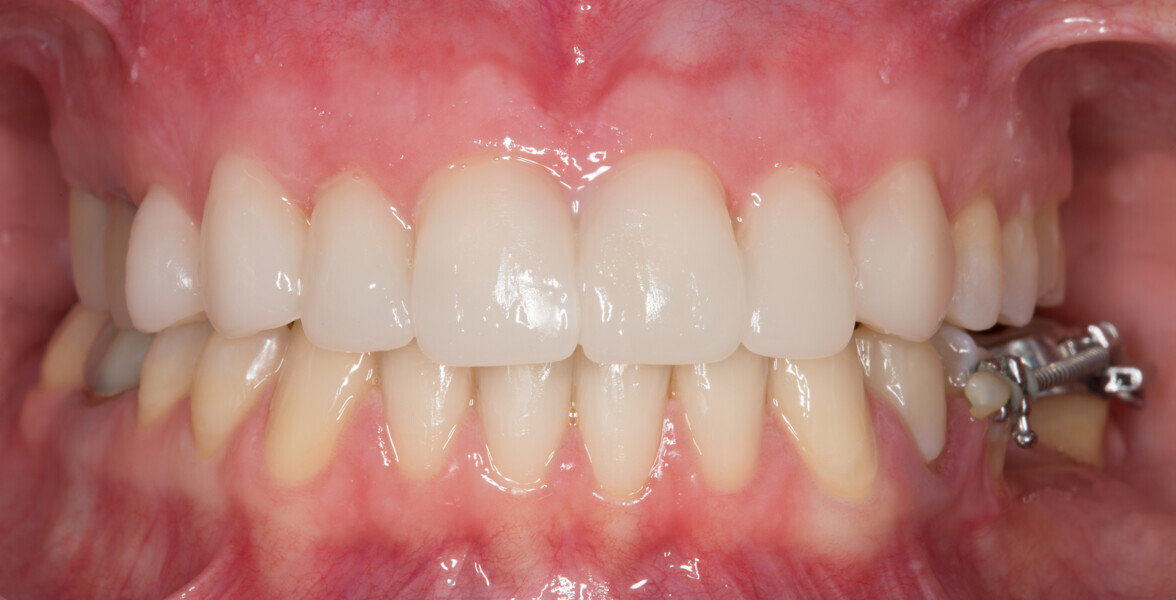

Fig. 16: Final analogue ceramic restorations.

Fig. 17: Final analogue ceramic restorations.

Fig. 18: Final analogue ceramic restorations.

Fig. 19: Final analogue ceramic restorations.